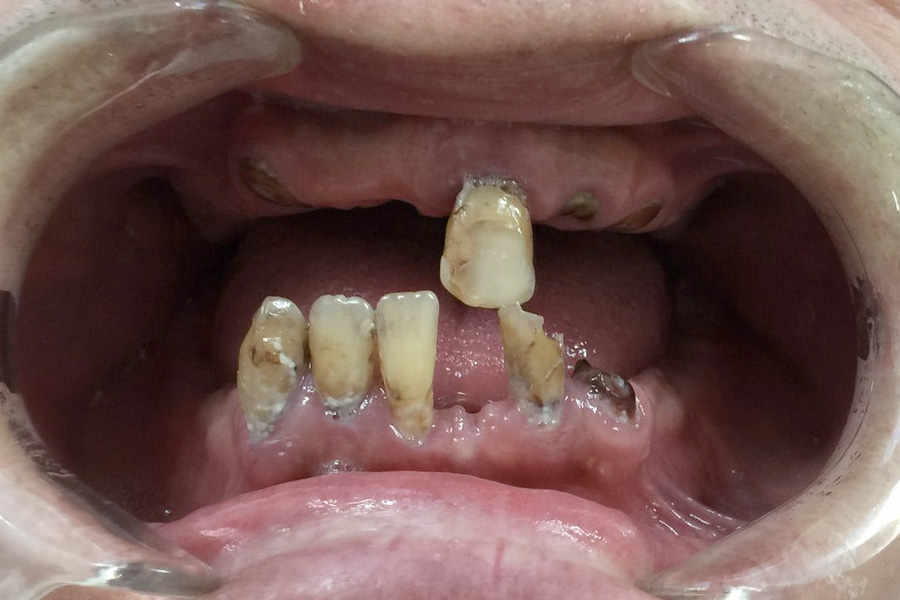

Emmerson’s remaining teeth had to be removed due to poor prognosis. He could not tolerate a conventional denture due to a hyperactive gag reflex.

The lower teeth were replaced utilising a All-on-Four technique. A fixed bridge of teeth was placed over four dental implants. In the upper jaw due to the limited availability of bone a removable over denture was made supported by four implants.